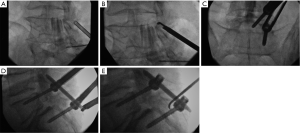

A retrospective review of every patient treated with this protocol was performed after approval of the local Institutional Review Board, and informed consent was obtained from each subject. Adult late middle aged to elderly patients with neuroimaging characteristics and a clinical exam consistent with neurogenic claudication due to focal spinal canal stenosis or discrete foraminal stenosis, combined with significant facet arthropathy and/or coexistent scoliosis were offered the combined procedure. All cases were performed in a biplanar neuroangiographic suite. After administration of a prophylactic antibiotic (1 gram either cefazolin or vancomycin), the patient was positioned prone and mildly sedated with intravenous midazolam and morphine sulfate. Local anesthesia in the lumbar skin, muscles and periosteum was achieved with a combination of 1% lidocaine and 0.5% bupivicaine. The pathologic target level was decompressed using a previously described percutaneous method of remodeling and resecting the ligamentum flavum and lamina (mild technique; Vertos Medical, Aliso Viejo, CA, USA) (4-6). In the mild technique, a 6 mm access cannula is percutaneously inserted via a 10 mm slit incision and using fluoroscopic control into the interlaminar region (Figure 1). One slit incision is required for each side of a target level. A set of single-use tools designed for working within the access cannula is then used to resect hypertrophic ligamentum flavum (tissue sculptor) and laminar/medial facet bone (bone sculptor, akin to a Kerrison rongeur). This portion of the procedure is performed under epidurographic control so as to clearly delineate the dural-epidural boundary and diminish the risk of unintentional durotomy. Bone fragments that were harvested from the lamina and medial facet involved with the stenotic segment during the decompression were saved for use in the fusion construct. Once the decompression had been completed, unilateral pedicle screw fixation was then achieved using commercially available percutaneous pedicle screw fixation techniques (Stryker, Allendale, NJ, USA; Biomet Spine, Parsippany, NJ, USA; Figure 2). If necessary, reduction of malalignment or scoliosis was gently attempted. Bone adjacent to the instrumentation on the facet and laminar surfaces was decorticated with a curette, and then the fusion construct was laid down lateral to the instrumentation. The fusion construct was composed of the laminar bone fragments, which were embedded into a bone-marrow aspirate-soaked allograft-derived demineralized bone matrix sponge (Osteosponge, Bacterin International Holdings, Belgrade, MT, USA) and demineralized bone matrix (Osteoputty, Bacterin International Holdings). The sponge, which acts as a malleable carrier as well as osteobiologic, is then inserted digitally onto the facet region through the pedicle screw access path, taking care to place the autograft bone fragments between the facet surface and the sponge. Skin incisions were closed in a single layer with 3-0 polyglycolic acid suture (Vicryl Rapide, Ethicon, Cincinnati, OH, USA). Patients were allowed to recover for 2–4 hours, then ambulated and discharged to home within 23 hours.

Thirteen patients were treated, and 3 were male (Table 1). The average age was 74 years (range, 58–87 years). Pathology included grade 1 spondylolisthesis, scoliosis, compression fracture, and facet instability, all of which were combined with stenosis. Levels treated ranged from L1 to L5 for mild decompression targets, and T10 to L5 for pedicle screw instrumentation and fusion (range of stabilization from 2 to 5 segments; Figure 3). The range of medications used during the procedure was as follows: midazolam, 2–4 mg; morphine sulfate, 5–8 mg; 1% lidocaine, 10–47 mL; 0.5% bupivicaine, 10–30 mL. All patients were easily arousable and cooperative throughout the procedure, and no procedure was aborted due to excessive movement or discomfort. Estimated blood loss ranged from 20–50 mL. Procedural time ranged from 108 to 197 minutes (average 153 minutes).